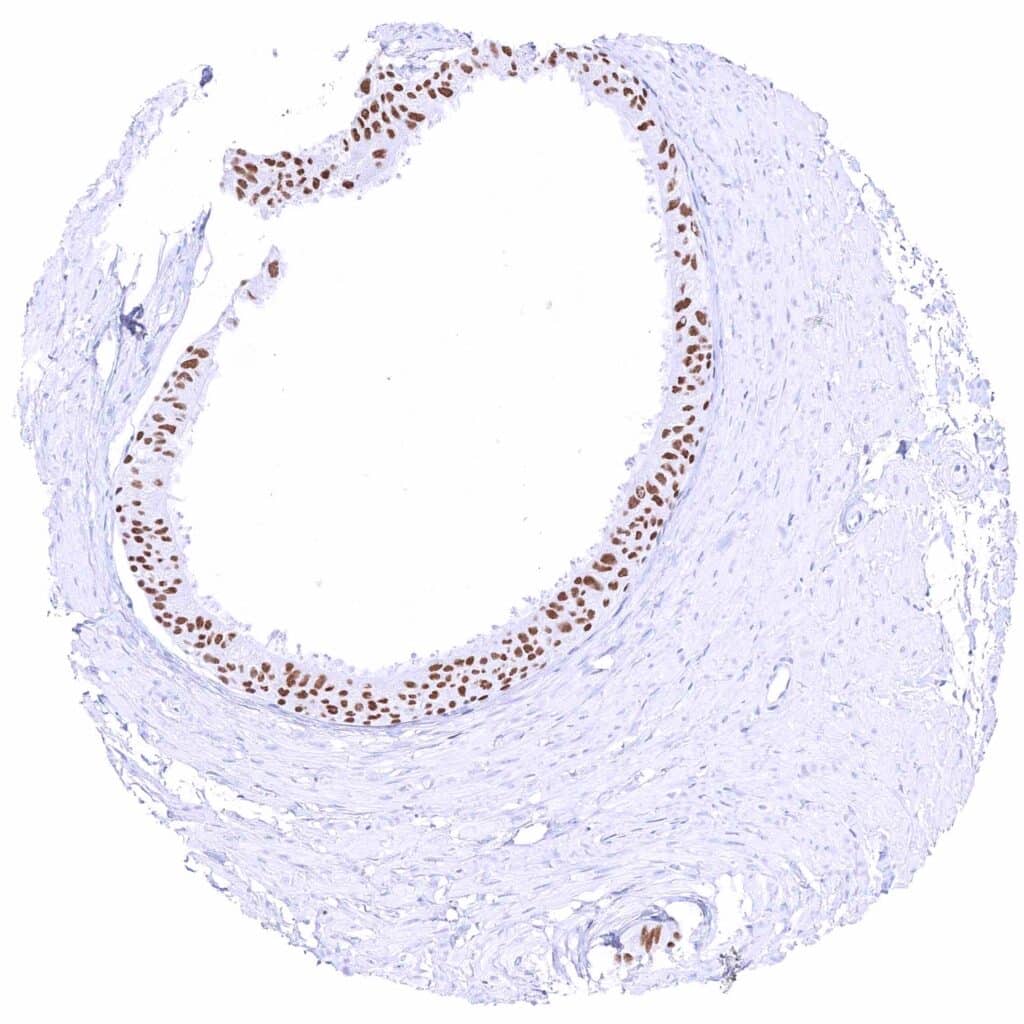

Kidney, pelvis, urothelium – Strong nuclear GATA3 positivity of all urothelial cells.